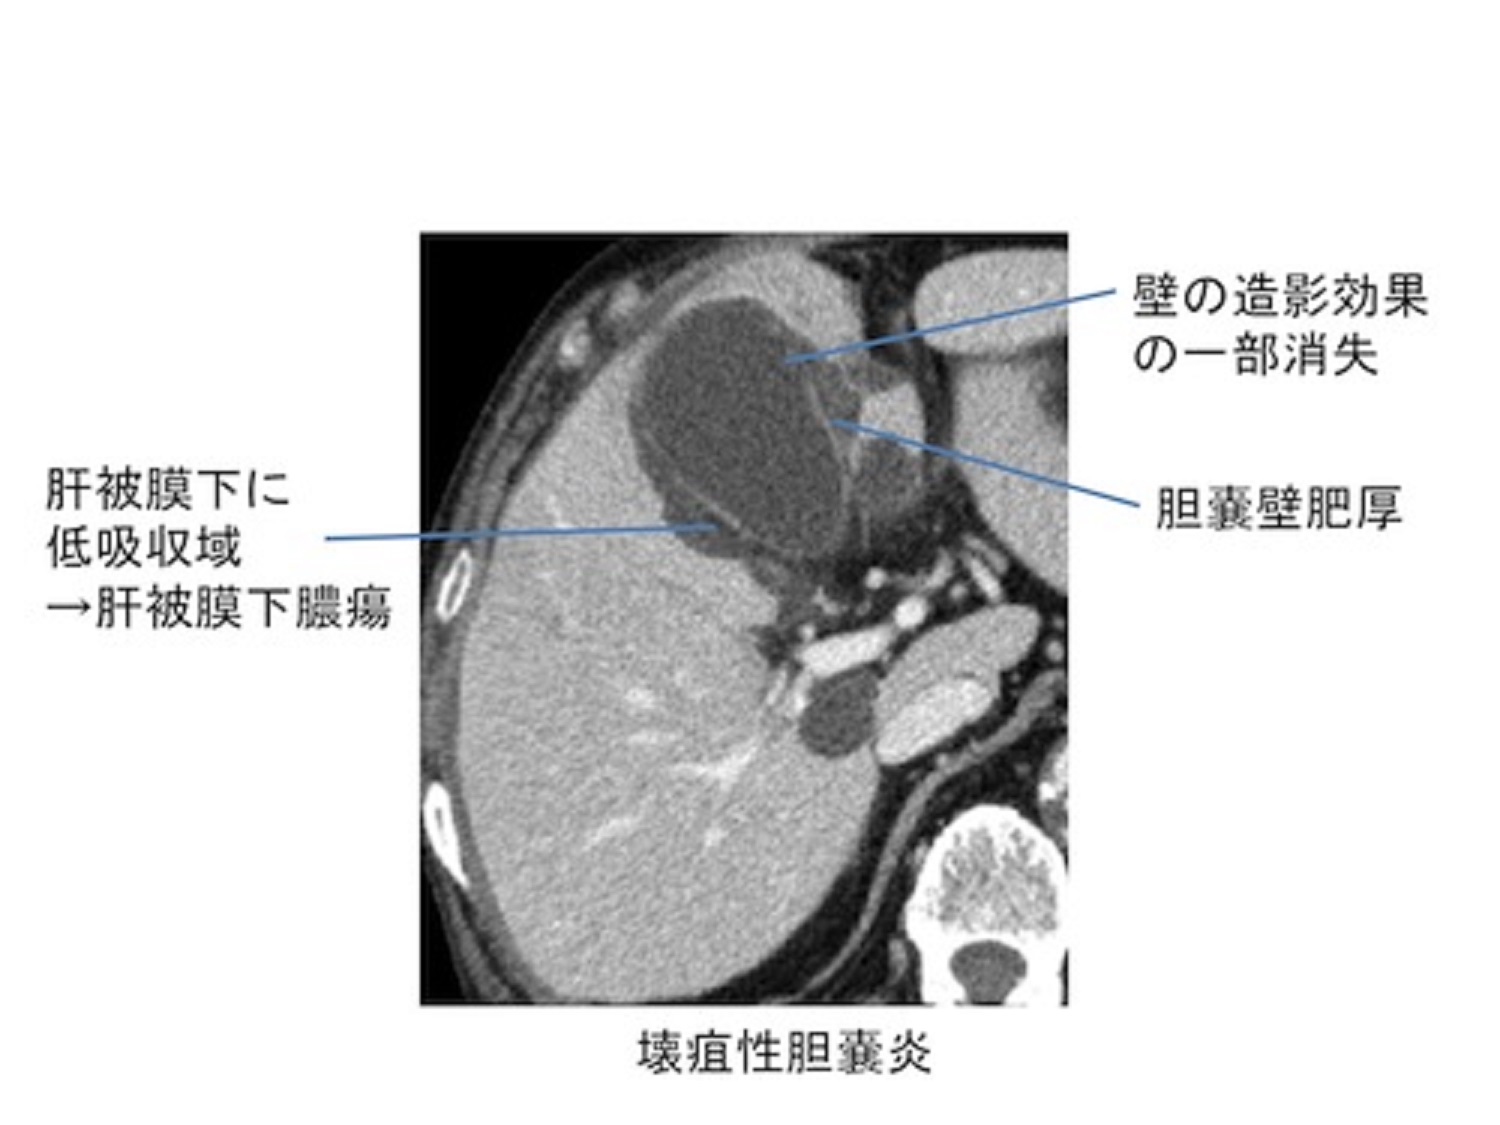

この状態は臓器の組織を急速に壊死させ、膿を蓄積させたり、穿孔を引き起こしたりするため、さらに深刻です。

これは長期にわたる外傷、火傷、大規模な手術、非経口栄養(体循環への直接の栄養の静脈内注入)に関連しており、高齢者でより一般的です。